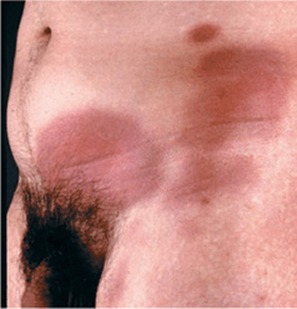

LİKEN PLANUS

Hastalığın kesin nedeni bilinmemekle birlikte, çevresel faktörler ve otoimmün bozukluklarla ilişkili olduğu düşünülen, ağız ve genital bölge başta olmak üzere vücudun çeşitli bölgelerini tutabilen enflamatuvar bir deri hastalığıdır. Kaşıntılı bir kızarıklığa sebep olur. 5p bulgusu. 1)pruritik 2)poligonal 3)purple 4)papül 5)parlak veya planar.

CloseLİKEN PLANUS

Hastalığın kesin nedeni bilinmemekle birlikte, çevresel faktörler ve otoimmün bozukluklarla ilişkili olduğu düşünülen, ağız ve genital bölge başta olmak üzere vücudun çeşitli bölgelerini tutabilen enflamatuvar bir deri hastalığıdır. Kaşıntılı bir kızarıklığa sebep olur. 5p bulgusu. 1)pruritik 2)poligonal 3)purple 4)papül 5)parlak veya planar.